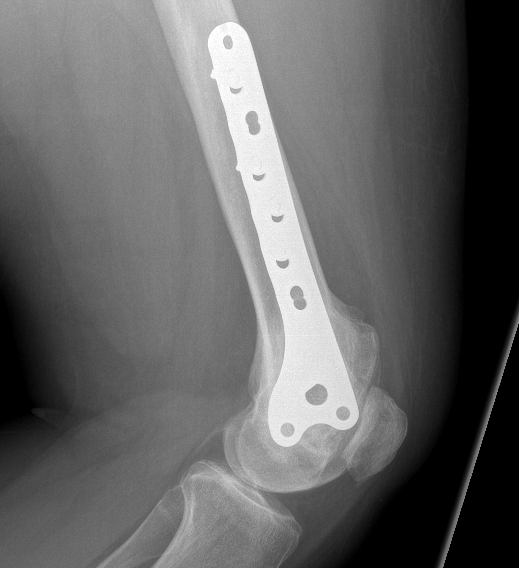

Currettage and Cement +/- local application phenol / liquid nitrogen

Technique

Open approach

- bone window

- remove tissue with curette

- saucerisation with high speed burr

- consider phenol / liquid nitrogen application

- cement (works by thermal necrosis), in addition to structural support

Results

- 354 GCT's treated surgically

- recurrence after curettage 18%

Knochentumoren et al JBJS Am 2008

- 384 cases

- recurrence significantly reduced by the use of cement